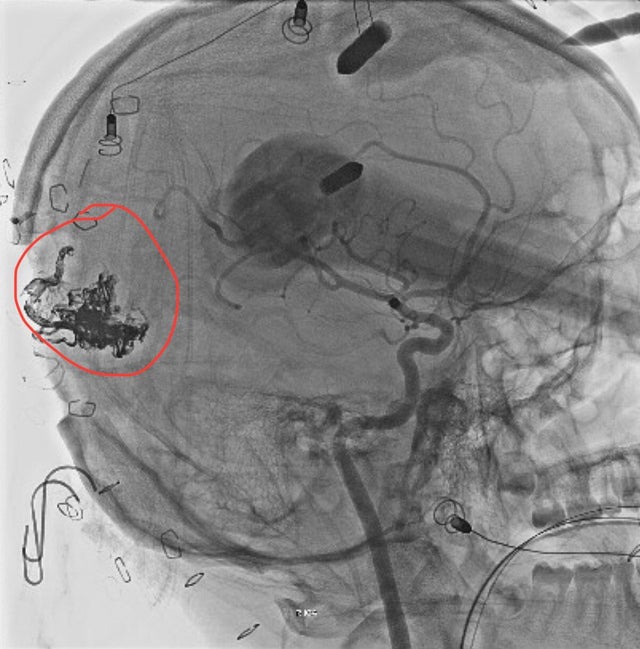

An AVM is an abnormal tangle of blood vessels in the brain, said Dr. Andrew Russman, head of the Cleveland Clinic's stroke program, who was not involved in Logan's care. AVMs put "a lot of pressure on the vein side" and can produce a variety of symptoms, he said. The biggest risk with an AVM is rupture, where the vessels burst and cause bleeding in the brain.

Riina said the AVM, which was on a "headache spot" in the occipital region of the brain, was likely the root of Logan's symptoms. People are born with AVMs, Riina said, and they grow as the body grows, which can cause increased symptoms.